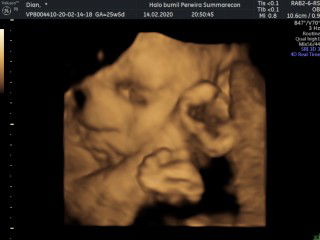

Usg 4D

Tggu loucing 21 maret ud gemes sm km nak Baby boy..

Imut nyaa... Bibirnya cemberut.. π